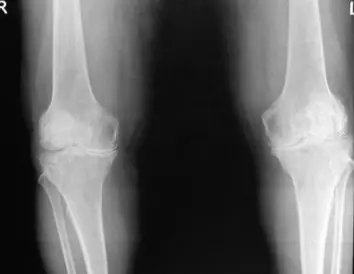

| Item | Procedure | Purpose/ Indication … | Attachment Links | Positive Finding/Interpretation |

| Look | Compare both limbs, Skin, Muscle bulk, bony landmarks, hair distribution | Assess symmetry, signs of trauma, inflammation, muscle atrophy, structural changes | Visual examples - Skin, Muscle, Bone, Joint: ![]() ![]() ![]() ![]() ![]() ![]() | Swelling, scars, discoloration, hair changes, muscle wasting, bony protrusions, angulation, redness |

| Joint-line tenderness, medial and lateral | Assess for meniscal or collateral ligament pathology | Joint lines: ![]() | Pain upon palpation along the joint line | |